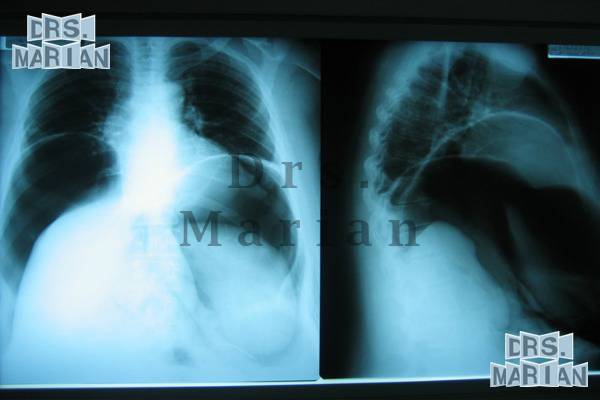

Giant Hernia

This type of hernia deserves a special mention, since the treatment starts from the preoperative management with the intra-abdominal catheter placement for the creation of a pneumoperitoneum (Introduction of air into the abdominal cavity). Depending on the case, if it were to apply one to two weeks before (there are reports of up to 3 months before) This has several functions, such as the pneumatic dissection of adhesions, the increase in volume of the abdominal cavity to facilitate the reintroduction of the viscera during surgery, in addition to providing the proper voltage for closure of the defect hernial sac.

If the pneumoperitoneum is superior to 3 weeks improves the quality of the response to the scarring, which is very important in this type of surgery